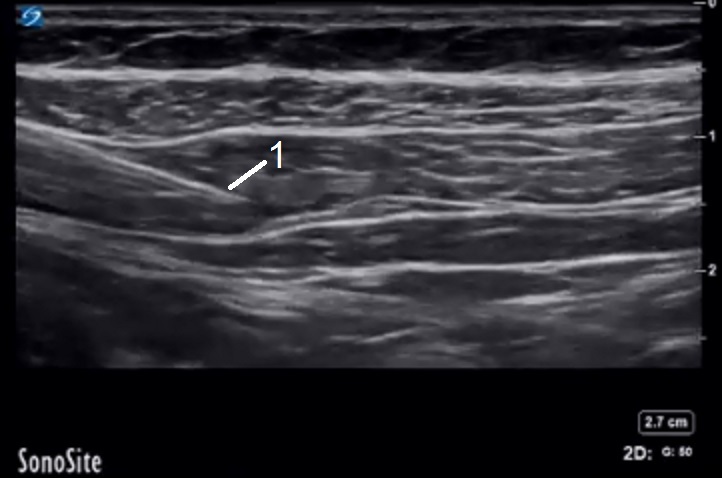

TAP Block 2 Image

Needle